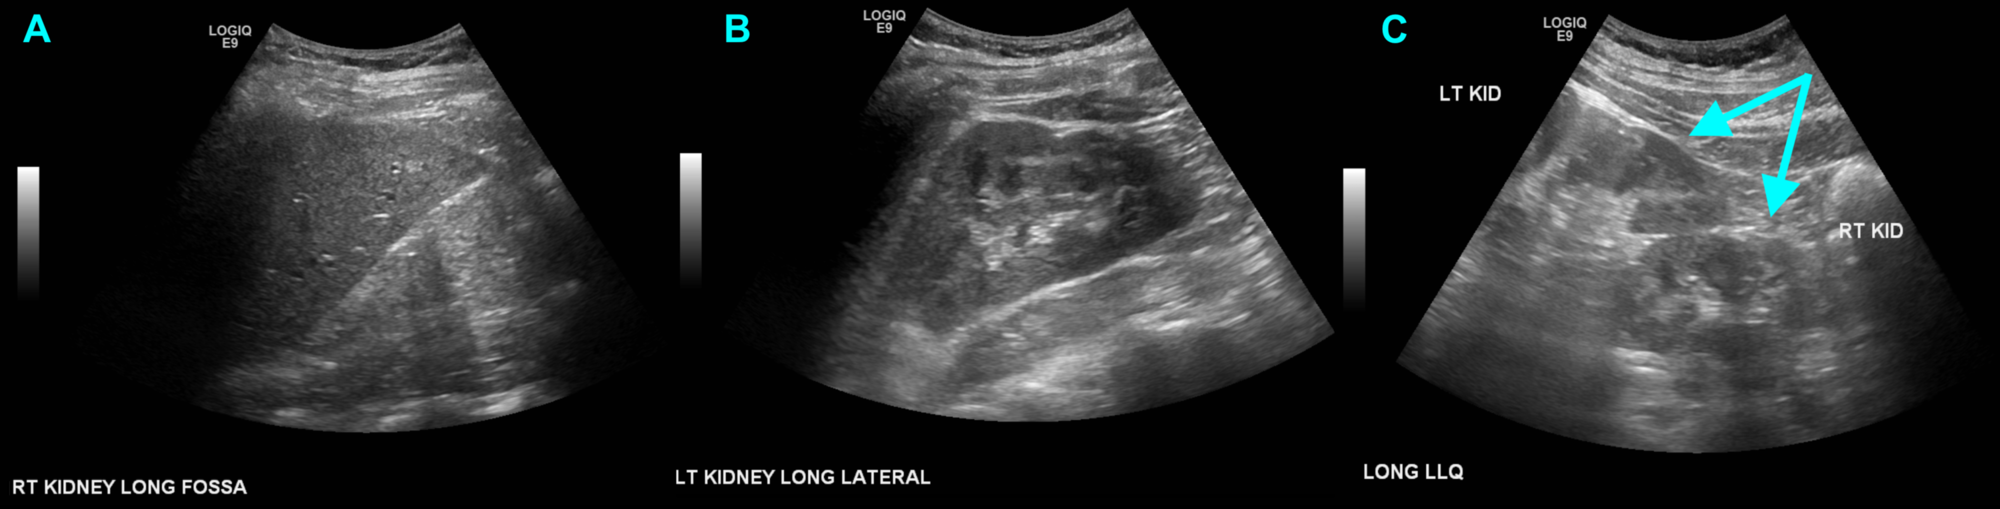

Ultrasonographic longitudinal images of kidneys in this case. (a,b Fused Kidney Ultrasound four types of crossed renal ectopia (fig 14) can be seen at imaging, mainly at ct and mri, including cre with fusion. Ultrasonography was found to be a good. ultrasound abdomen and pelvis, micturating cystourethrogram, and radionucleotide scans were the imaging modalities preferred for. renal bladder ultrasound (rbus) is a good tool for establishing the diagnosis, however,. Fused Kidney Ultrasound.